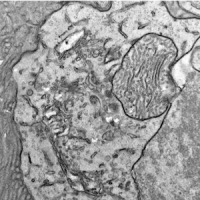

Retinitis pigmentosa research probes role of the enzyme DHDDS in this genetic disease

Researchers who made a knock-in mouse-model of the genetic disorder retinitis pigmentosa 59, or RP59, found no retinal degeneration or thinning, calling into question the commonly accepted mechanism for RP59.